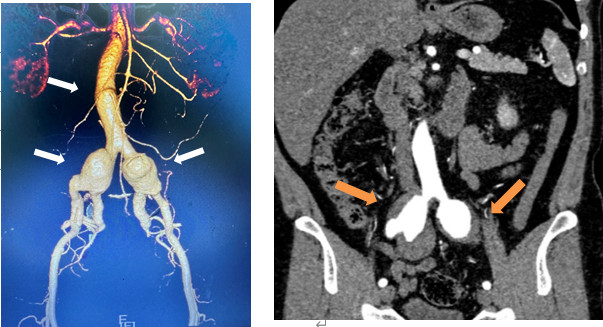

術前CTA提示腹主動脈局限性瘤樣擴張及雙髂動脈瘤并附壁血栓(箭頭所示)。

文叔今年53歲,在一個多月前的體檢中,意外查出雙側髂動脈擴張。進一步的CT檢查提示:雙側髂總動脈及髂內動脈近端動脈瘤,伴附壁血栓形成。這意味著,文叔體內就像埋了隨時會爆炸的炸彈:動脈瘤一旦破裂,后果不堪設想。

文叔隨即來到福建省人民醫(yī)院血管外科求治。檢查發(fā)現(xiàn),他體內一連串動脈瘤中最大的直徑已超過4厘米,瘤體內有大量血栓,與輸尿管、髂靜脈、膀胱等重要組織緊緊粘在一起。